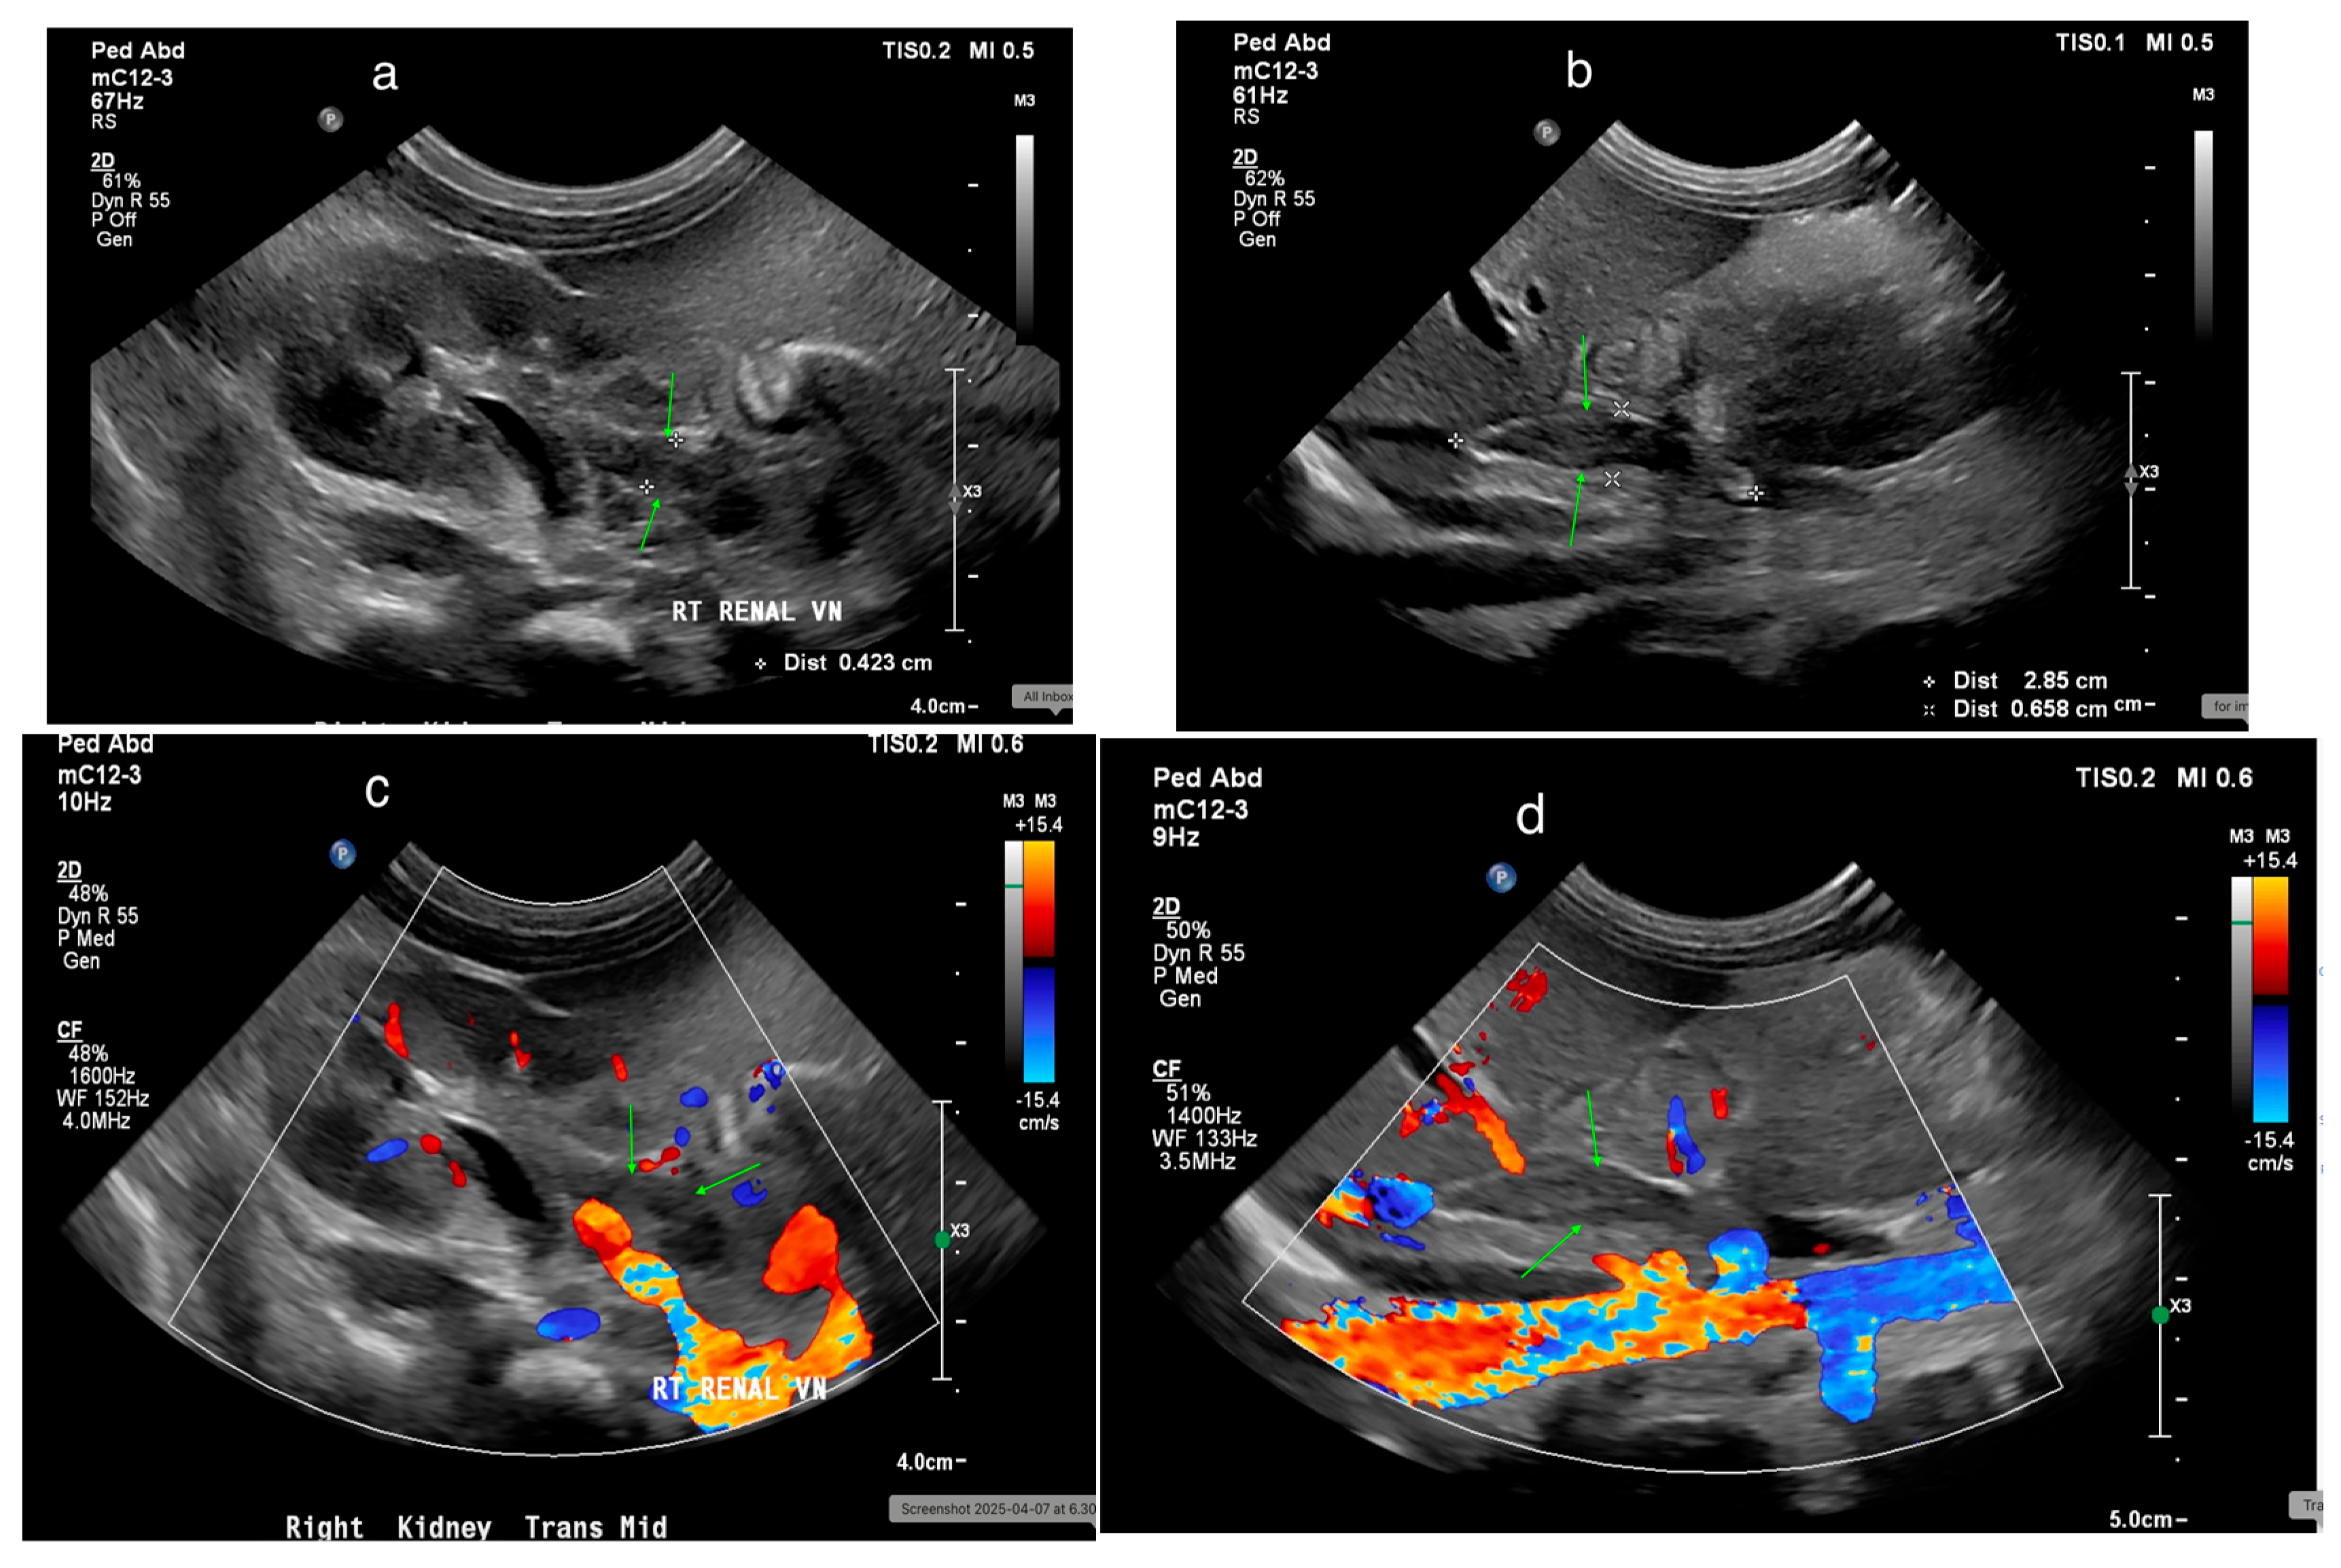

Figure 25. (a) Thrombosis in the renal vein (green arrows) in a 7-day-old male. (b) Thrombosis in the inferior vena cava (IVC) (green arrows) in a 7-day-old male. (c) Doppler ultrasound (US) shows minimal flow around the thrombus in the right renal vein (green arrows). (d) Doppler US shows no flow around the thrombus in the IVC (green arrows).

US effectively detects renal vein thrombosis (RVT), with its appearance varying over time. In the first few days, echogenic streaks may appear due to thrombi in interlobular and interlobar veins [82]. By the first week, kidney enlargement and an echogenic cortex may develop. Later, corticomedullary differentiation loss becomes prominent, and thrombus calcification may be seen [83]. US can also detect thrombi in the renal vein and inferior vena cava (Figure 25a,b). Doppler US may show an elevated resistance index (RI) and absent renal venous flow (Figure 25c,d) [82,83].